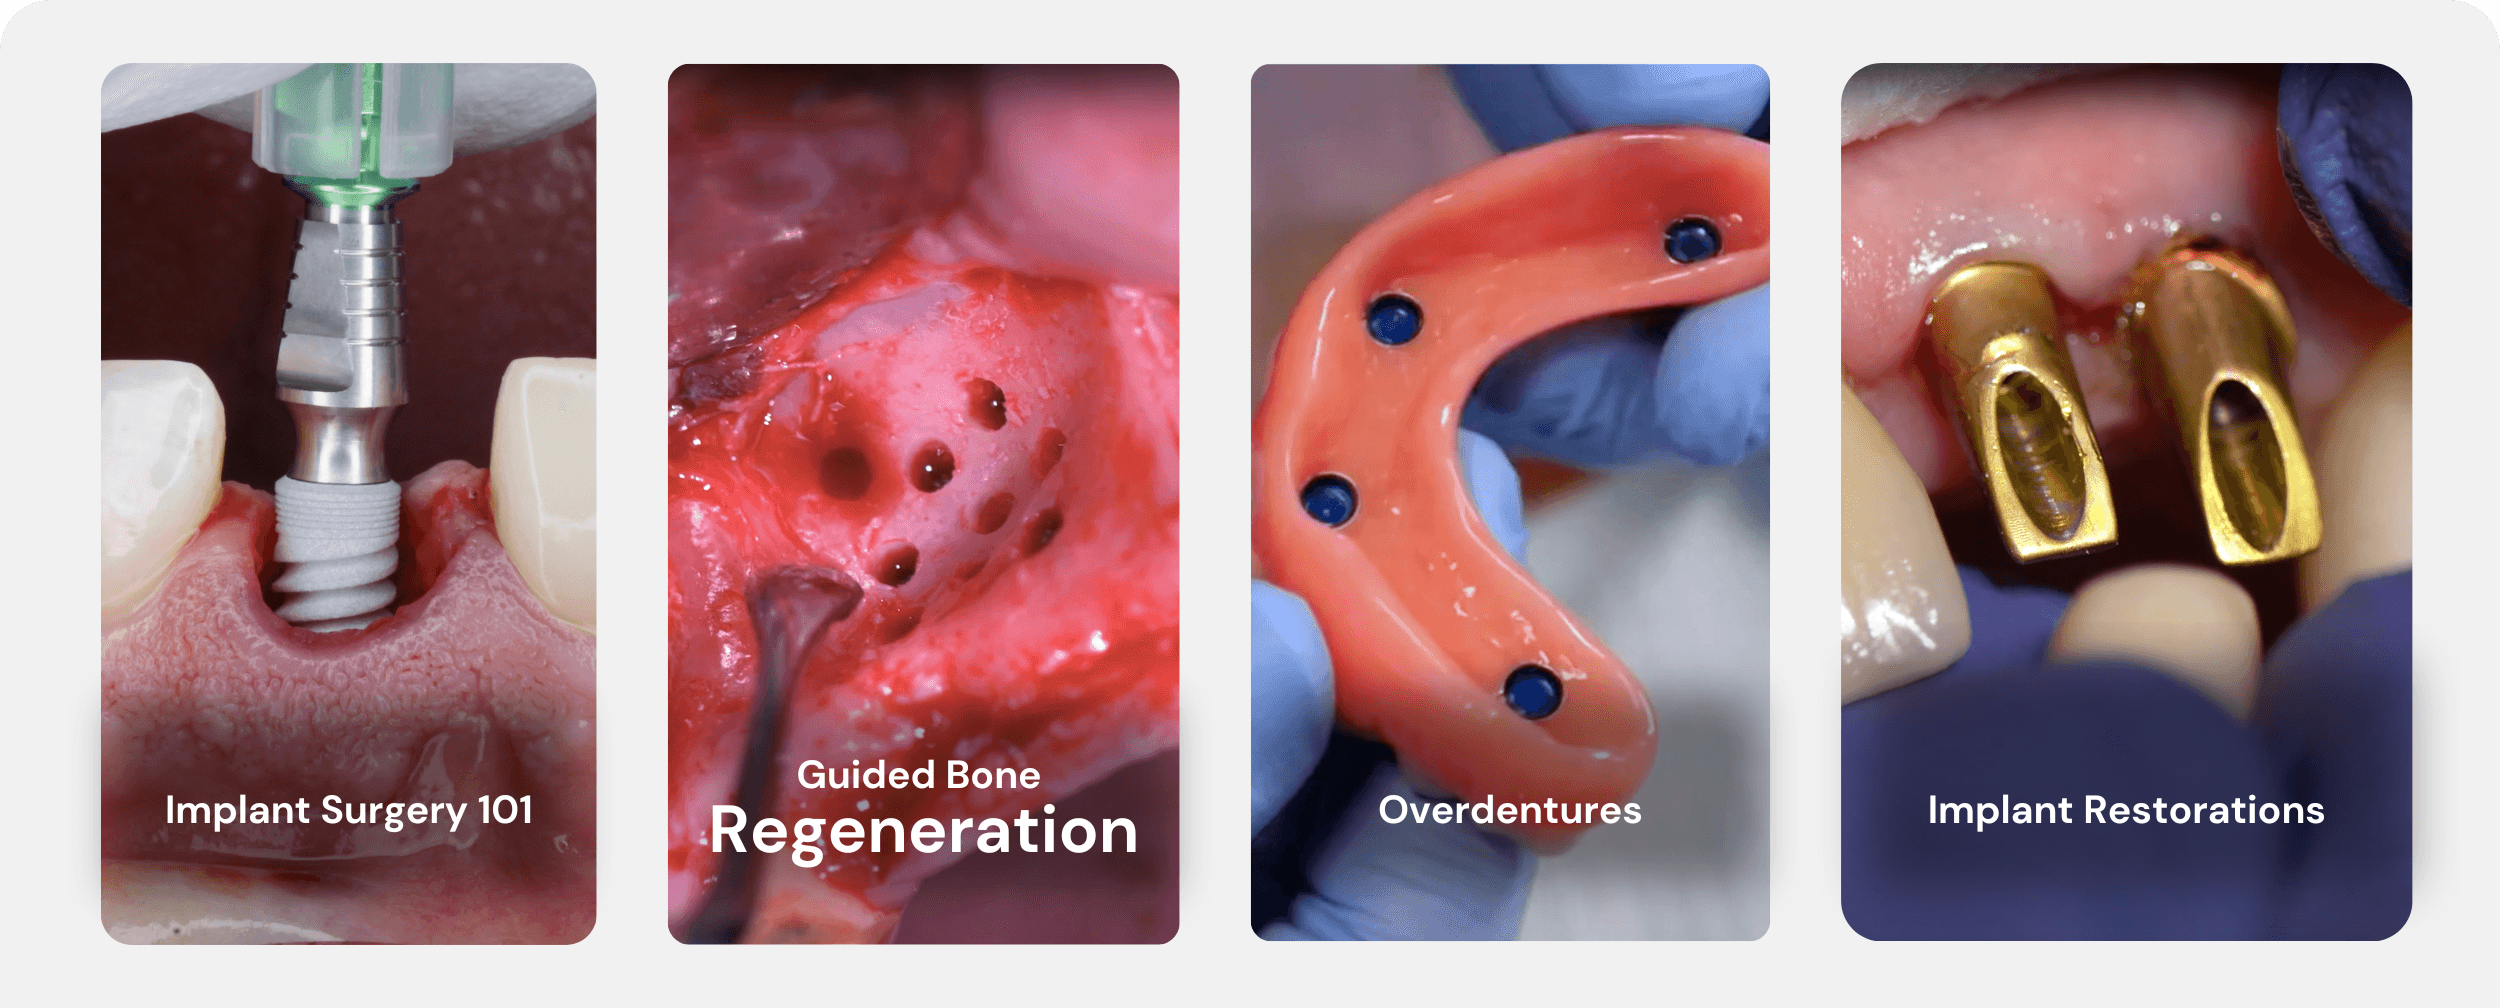

Supporting the full implant treatment process

Supporting the full implant treatment process

Supporting the full implant treatment process,

Evolution Spine New Product Launch – Ortho Spine News, All on X Course - Implant Ninja | We Make Implants Simple.

All on X Course - Implant Ninja | We Make Implants Simple.